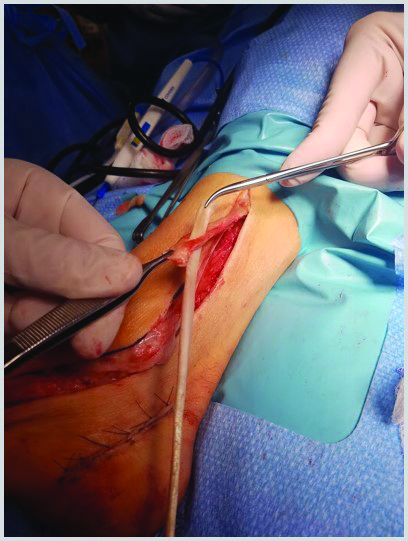

We utilized a two-stage approach for peroneal tendon reconstruction. In the first stage, we utilized a silicone Hunter rod replacement in order to establish a peroneal tendon pseudosheath to allow gliding function of the reconstructed tendon allograft. In the second stage, we performed a lateral calcaneal slide osteotomy to correct the varus heel position. We also incorporated the tendon allograft into the peroneus brevis muscle and fifth metatarsal base through minimal incisions with the foot in a maximally-tensioned dorsiflexed and abducted position.

In this scenario, the gliding function of the peroneal tendon sheath remained intact as well as the peroneal musculature. Thus, we performed excision of the dysfunctional peroneal tendons. We also applied a tendon allograft, performed a Dwyer calcaneal osteotomy and lengthened the posterior tibial tendon as a single-stage procedure.